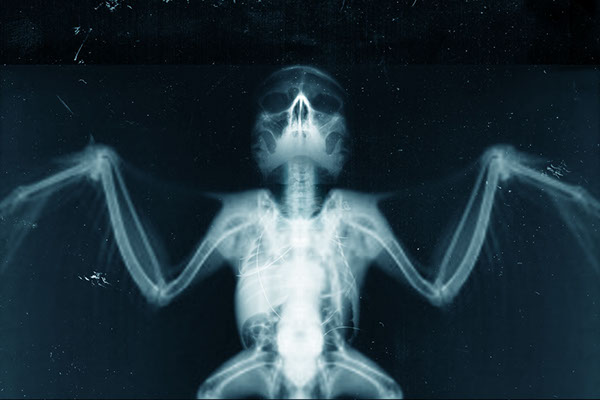

Необычные рентгеновские снимки: то, что скрыто внутри

Раздел: Визуальный дайджест